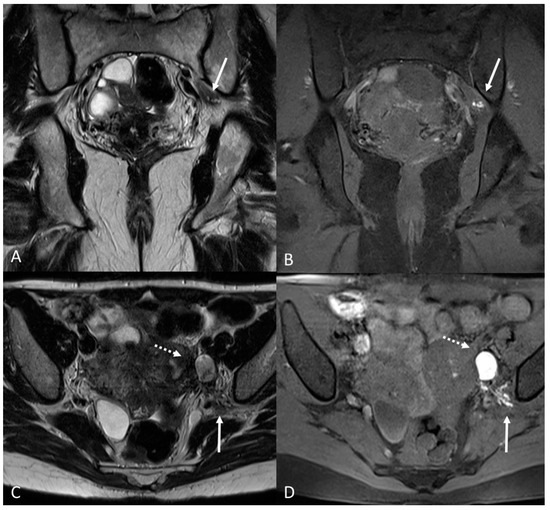

There are also cases of involvement of peripheral nerve plexuses of the pelvic region, such as sciatic, obturator, femoral, and pudendal nerves and their branches (Figure 14).

Figure 14.

Localization of the left sciatic nerve and para-uterine endometriotic nodule in a 43-year-olf female with a previously diagnosed endometriosis and surgery approach, accepted at the emergency department for reported left lumbar pain, which radiates to the left side and is associated with episodes of vomiting. (A) Coronal T2WI. Involvement of peripheral nerve plexuses of the pelvic region (sciatic nerve) appearing as a hypointense plaque (white arrow); (B) Coronal fat-suppressed T1WI. The lesion shows small hematic foci (white arrow); (C) Axial T2WI. Para-uterine endometriotic nodule (white dotted arrow) shows variable intensity ranging from low intensity (referred to as shading) to intermediate or high intensity; (D) Axial T1WI. Para-uterine endometriotic nodule with hyperintense signal (white dotted arrow).

MRI is the best imaging modality to investigate neural involvement [78].

In this paragraph, we will explore the main signs in post-operative imaging in order to provide the radiologist with an indication to evaluate MRIs of women with extensive and complex endometriosis undergoing surgery (Figure 15 and Figure 16).

Figure 15.

Para-uterine fluid collection in a 43-year-old female who underwent several gynecological surgeries for deep infiltrative endometriosis. (A) Axial T2WI. Compartmentalized hyperintense collection in the left para-uterine area after pelvic surgery (white arrow). (B) Coronal T2WI. Endometriotic localization of the vescico-uterine pouch (black arrow).

Figure 16.

Localization of endometriosis in the left parametrium and ureteral stenosis in 49-year-old female who underwent supracervical hysterectomy, bilateral salpingectomy and mild vaginal bleeding and abdominal pain. (A) Axial T2WI; (B) Sagittal T2WI. Endometriotic localization of the left parametrium (white arrow), with irregular margins and heterogeneous signal intensity. Tractions towards the sigmoid colon, left pararectal fascia, anterior pelvic peritoneal reflection and adnexa. Ureteral stenosis caused by the parametrial plaque (dotted arrows in (B)). (C) Axial T2WI; (D) Axial fat-suppressed T1WI. Endometriotic nodule of the left pelvic wall (white arrow).